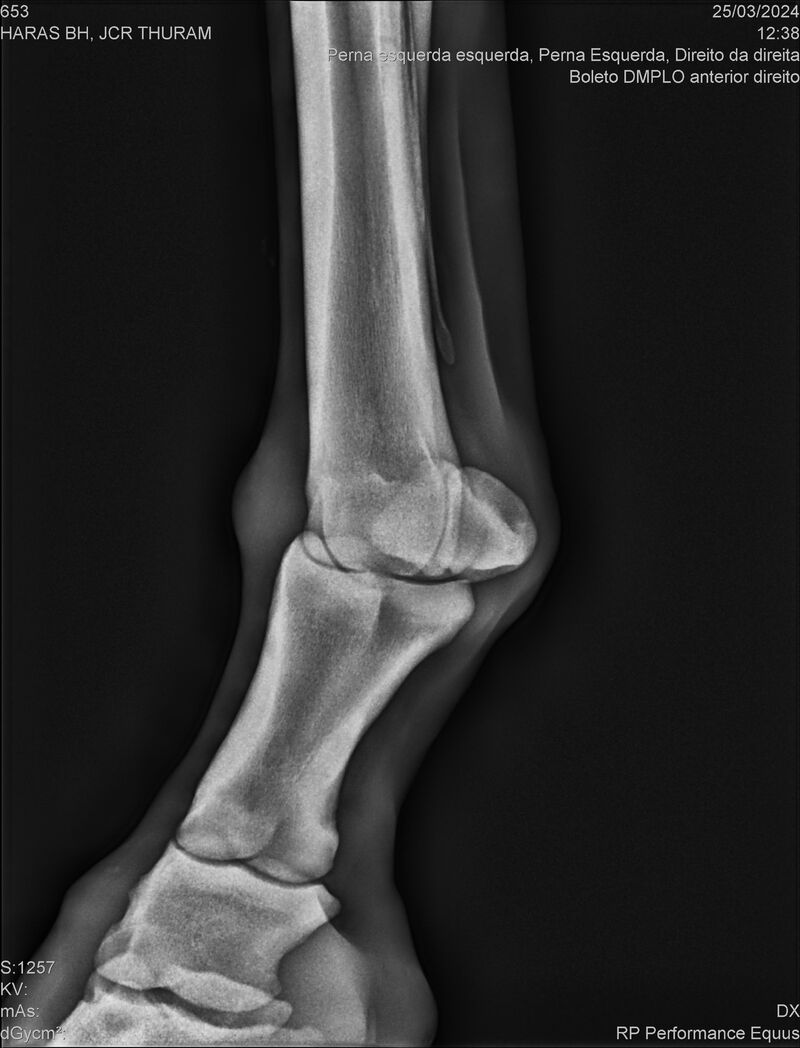

JCR THURAM

Raça: BRASILEIRO DE HIPISMO

Sexo: CASTRADO - CASTRADO

Nascimento: 10/01/2021

Registro: 27531-BH

Vend.: HARAS BH